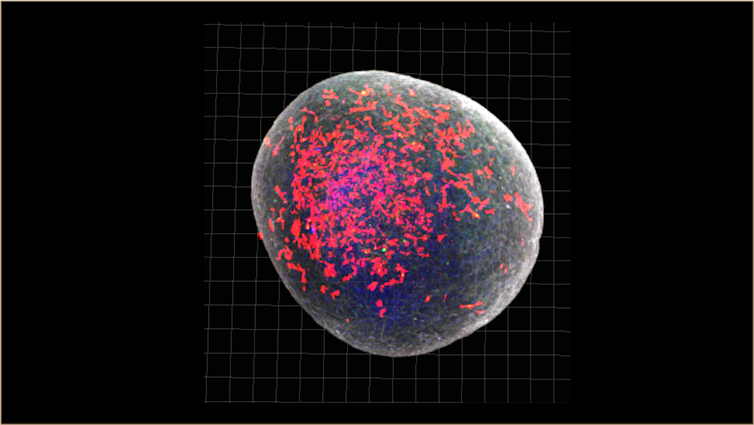

In a recent study, we created brain organoids a little bigger than a pinhead and infected them with SARS-CoV-2, the virus that causes COVID-19.

In these organoids, we found that an excessive number of synapses (the connections between brain cells) were eliminated – more than you would expect to see in a normal brain.

One of the crucial functions of the brain’s immune cells, or microglia, is to prune these inactive synapses.

The exaggerated elimination of synapses we saw in the COVID-infected models could explain why some people have cognitive symptoms as part of long COVID.

By sequencing the RNA of single cells, we could study how different cell types in the organoid responded to the virus. We found that the pattern of genes turned on and off by the microglia in our COVID-infected organoids mimicked changes seen in neurodegenerative disorders.